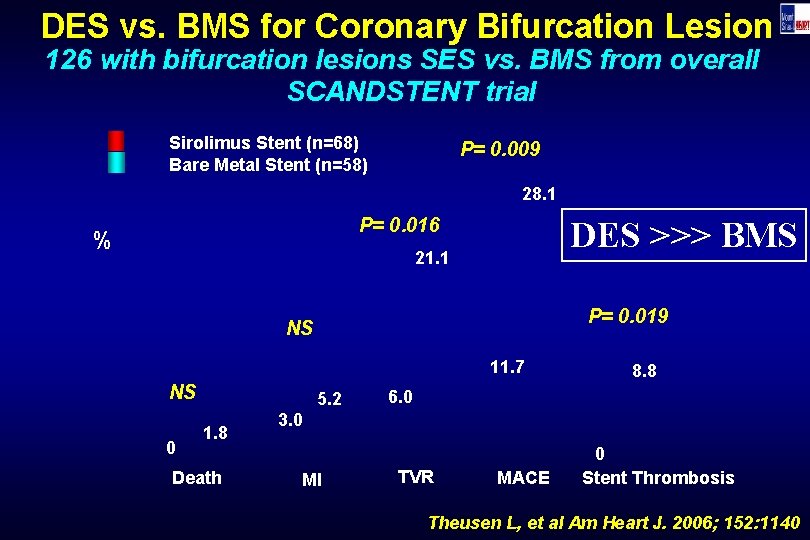

DES vs. BMS for Coronary Bifurcation Lesion 126 with bifurcation lesions SES vs. BMS from overall SCANDSTENT trial Sirolimus Stent (n=68) Bare Metal Stent (n=58) P= 0. 009 28. 1 P= 0. 016 % DES >>> BMS 21. 1 P= 0. 019 NS 11. 7 NS 0 5. 2 1. 8 Death 8. 8 6. 0 3. 0 MI TVR MACE 0 Stent Thrombosis Theusen L, et al Am Heart J. 2006; 152: 1140